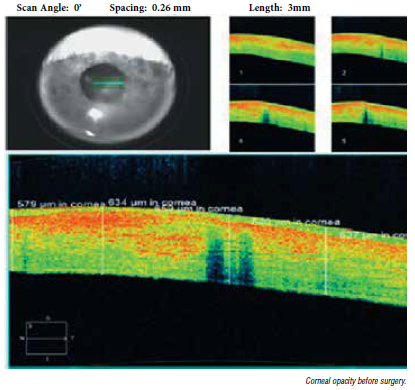

Stromal lenticule implantation may reduce recurrence of herpetic keratitis. Roibeárd O’hÉineacháin reports from the ESCRS Virtual Winter Meeting 2022. In patients with chronic recurrence of herpetic keratitis, removing a corneal scar with small lenticule extraction (SMILE) procedure and replacing it with a healthy lenticule of equal volume from a donor undergoing a myopic SMILE procedure can restore corneal clarity, improve vision, and may also reduce the likelihood of further recurrence of the condition, reported Anita Syla Lokaj MD, ophthalmologist at Eye Hospital in Kosovo. At a Cornea Day session, Dr Syla Lokaj described the case of a 45-year-old male patient who underwent a tissue extraction procedure for recurrent herpetic keratitis in his right eye. Prior to surgery, the eye’s corneal thickness—as measured by anterior segment optical coherence tomography (AS-OCT)—and decimal visual acuity were 0.1. AS-OCT also revealed the presence of dead keratinocytes within the scar tissue. The herpetic keratitis patient and the patient undergoing refractive SMILE surgery underwent their surgery on the same day by Dr Faruk Seimz. The donor patient underwent the usual serology tests to ensure the absence of any transmissible disease. The extracted donor lenticule were placed in BSS solution for five minutes. The surgeon then prepared the stromal pocket with the femtosecond laser and implanted the lenticule through a side-pocket incision. The lenticule was over 100 μm in thickness to include live keratinocytes. At a follow-up of 36 months, the cornea thickness remained stable, and slit-lamp biomicroscopy showed good organisation of collagen fibres. Corneal topography also showed a beneficial decrease in improvement in keratometric values. In addition, by three months, decimal visual acuity improved to 0.3 and by six months, it had improved further to 0.5 and has since remained stable throughout follow up. “The stromal haze has cleared, and at a follow-up of three years, we detected no sign of recurrence of herpetic keratitis. We implanted the donor lenticules with live keratinocytes not only in this case but in all cases so they could produce collagen. We have found good transparency of the cornea in all the [patients] in which we have performed this procedure,” Dr Syla Lokaj said. She noted herpetic eye disease is the most common infectious cause of corneal blindness in developed countries and accounts for 60% of corneal ulcers in developing countries, affecting 10 million people worldwide. In addition, the rate of ocular recurrence after one episode is about 10% at one year and 50% at 10 years. And although oral acyclovir reduces the risk of any form of recurrence of ocular herpes by 41% and stromal keratitis by 50%, it still leaves a lot of patients with recurrences. Moreover, acyclovir’s protective effect does not persist after withdrawal of the treatment. “Our early findings suggest [using] corneal stromal lenticules with stromal stem cells and live keratocytes [can] be a safe and Schematic representation of the diameter of the lenticule to be implanted, the diameter of the intrastromal pocket, incision width, and the implanted position of the lenticule in the recipient cornea. efficient surgical treatment for stromal scar after herpetic keratitis. This is a relatively simple and low-cost procedure that offers advantages over corneal transplantation as a definitive procedure in the treatment of this disease,” Dr Syla Lokaj concluded. Anita Syla Lokaj MD is an ophthalmologist and PhD candidate at the Eye Hospital in Pristina, Kosovo. anitasylaj@live.com